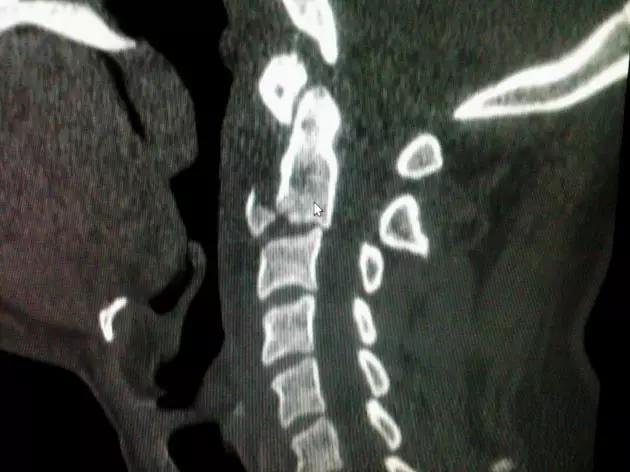

脊柱骨折

1. Burst 骨折

椎体轴向压力造成的骨折,通常发生骨折碎片向外侧的移位。可以发生在颈椎、胸椎或腰椎。

(来源:Radiopaedia)

2. Teardrop 骨折

特指颈椎椎体前下方带有骨折块者,包括屈曲型和伸展型。伸展型损伤指椎体前下缘或下一椎体前上角形成三角形骨块,提示椎体前方稳定结果破坏,治疗不宜伸展位。屈曲型指压缩致使椎体前方三角骨块被挤出如泪滴状,提示前后方稳定结构均遭破坏,常伴脊髓损伤。常需手术治疗。

伸展型 Teardrop 骨折(来源:Radiopaedia)